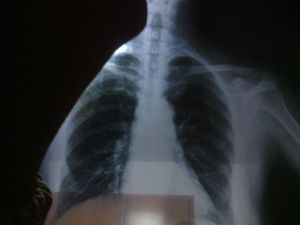

結節病(sarcoidosis)為一種可侵犯全身多系統的慢性疾病,90%累及肺,其基本病變為形成非乾酪樣壞死性肉芽種。該病多見於中、青年女性,以肺、肺門淋巴結最常受累,也可累及淺表淋巴結、皮膚、眼、扁桃體、肝、脾、骨髓等處。